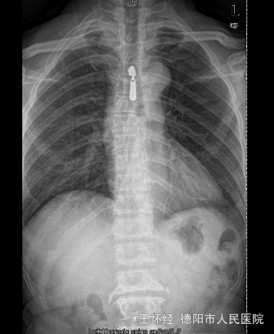

患者男,52岁,因“车祸伤后右肩部、右胸壁疼痛伴右上肢活动障碍1+天”入院。入院1+天前,患者因车祸伤致右肩部疼痛、有胸壁疼痛、右上肢活动障碍、无法上抬,无明显麻木,右胸锁关节处可见一明显隆起硬块、压痛明显,同时自觉少许呼吸困难,我院急诊行X光片示“右胸锁关节脱位”,遂收住我科。

查体:右侧胸锁关节处叩压痛明显,可扪及一隆起、质硬,右侧胸壁乳头周围肿胀,右肩外展因胸锁关节处疼痛而受限受限。 辅查:X片及CT提示示右侧胸锁关节向前脱位、双侧第一肋骨骨折

初步诊断:车祸伤:1.右侧胸锁关节前脱位;2.双侧第一肋骨骨折。 诊疗计划:右侧胸锁关节脱位切开复位,锚定固定修复关节囊及周围韧带。